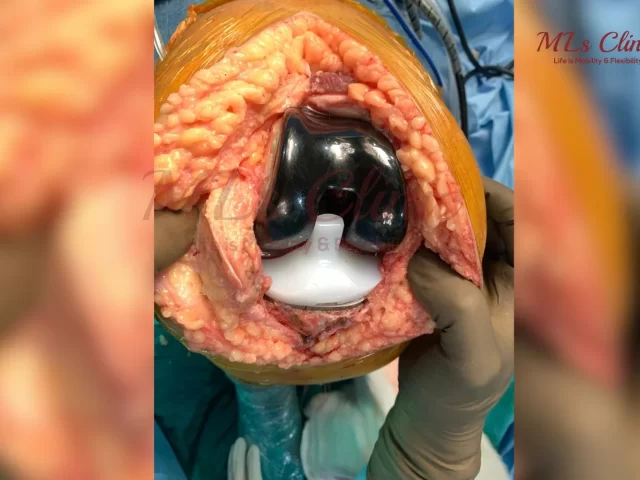

Knee Implant Materials: Titanium, Cobalt, Zirconia – Finding the Best Fit for You!

Are you also the one who is suffering from constant Knee Pain? Are you the one who has been told...

Need a Knee Replacement? Which types of Knee Implants are right for you?

Knee injuries are another very common issue affecting millions of people worldwide. Whether it be arthritis, Age factor or any...